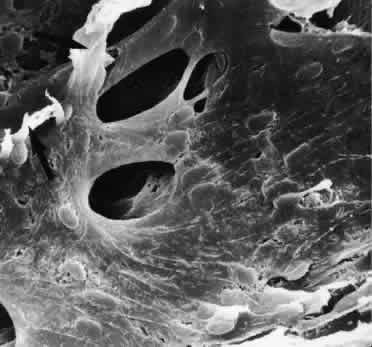

OUTFLOW CHANNELS OF SCHLEMM'S CANAL

After passing through the TM, aqueous humor enters Schlemm's canal and then the collector channels. Schlemm's canal is not a uniform vessel but is often divided into different parts by bridges or septa.79 The septa cross the lumen of the canal mostly in an oblique direction. They are often fixed to the outer wall of the canal at places where the collector channels begin. Thus the septa, which often form twisted or spiral bands, can be considered to be guiding structures for aqueous humor toward the openings of the collector channels (Figs. 24 and 25). Some bridges do not cross the entire lumen of the canal but remain part of the outer wall, adjacent to a collector channel entrance. The number and form of septa and bridges vary to large extent. There are also regional differences with regard to form, number, and development of these structures.

Fig. 24. A and B. Scanning electron micrographs of sagittal sections of the trabecular meshwork and Schlemm's canal of human eyes showing different types of septa and intracanalicular bridges (arrows; A, × 500; B, × 620).

Fig. 25. Scanning electron micrograph of the outer wall of Schlemm's canal in a human eye showing a group of openings that lead into collector channels. Two pillar-like septa (arrows) are disrupted (× 1,200).

The structure of the outer wall of Schlemm's canal differs very much from that of the inner wall. The endothelial lining is single-layered, with a well-developed basement membrane. The cells do not possess transcellular microchannels. The adjacent stroma consists of collagenous and elastic-like fibers intermingled with fibroblasts.

The 25 to 35 collector channels drain the aqueous humor toward the intrascleral or episcleral venous plexus.1,2,79 Two different types of collector channels can be distinguished (Fig. 26). Direct channels run directly toward the episcleral plexus without any connections with the intrascleral vessels. If these channels contain aqueous humor, they can be identified in the limbal region as “aqueous veins.”80 In the human, normally only four to six direct channels exist. The indirect collector channels, which are more numerous nasally than temporally, join the intrascleral venous plexus in various distances from Schlemm's canal.